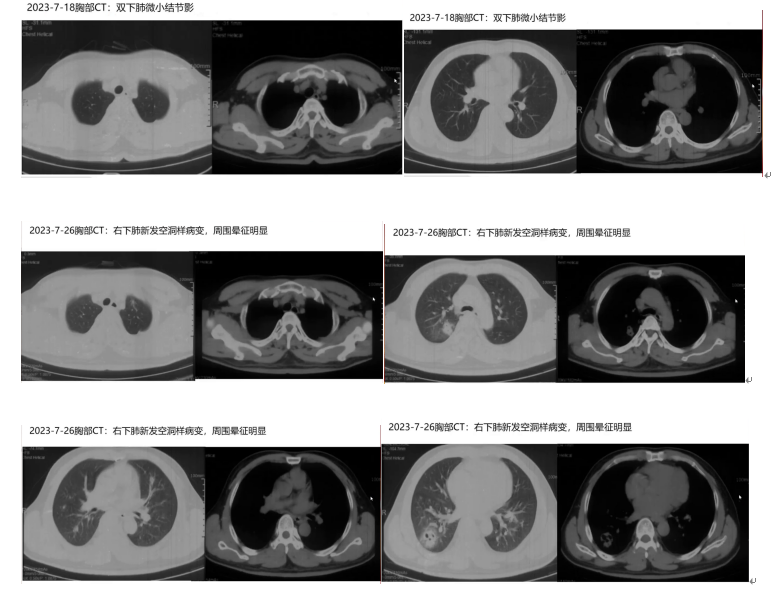

患者入院1月余前无明显诱因出现发热,体温最高39.0℃,伴有咳嗽、咳痰,每日约十几口痰,偶有痰中带血丝,无胸痛、胸闷、气短、头痛等不适,自诉自测新冠抗原阳性。2023-7-18胸部CT可见双下肺微小结节影,服用先诺特韦/利托那韦片5天治疗,仍间断发热,伴有咳褐色样黏痰。2023-7-26复查胸部CT可见双肺多发结节、斑片状影,右下肺可见空洞样病变,周围晕征明显。2023-7-26晚间患者无诱因出现右侧肢体活动障碍,走路不协调、无法持筷、言语不流畅,无晕厥、头痛、意识障碍、二便失禁、呛咳、肢体麻木等不适。当日患者就诊于北京某院,血常规提示白细胞36.59×10⁹/L,咽拭子示新冠核酸检测阳性,四肢血管超声无异常,头CT:左枕叶、左侧脑室旁、左侧额顶叶多发低密度影,结合病史考虑转移灶,其中左枕叶伴出血可能,双侧额窦、上颌窦及右侧蝶窦炎可能。诊断考虑急性白血病伴脑转移,经抗病毒、抗真菌等对症治疗后症状无明显改善,遂转入本科室。

影像学检查

胸部CT显示双肺多发结节、斑片状影,右下肺空洞样病变较前实变;头颅增强MRI提示左侧额叶脑室多发脓肿病灶且脓肿壁强化;浅表淋巴结超声提示腹股沟和腋窝多发肿大淋巴结。